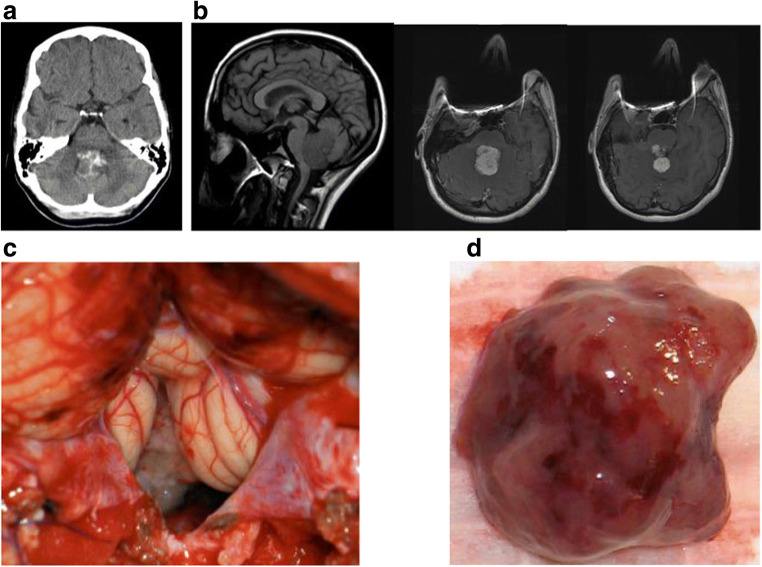

Six patients had signs of hydrocephalus on imaging. On pre-contrast CT, the lesions were heterogenous, lobulated, and hyperdense relative to the surrounding brain. Various degrees of calcification were observed in four patients (33%) (Fig. 1a). MR imaging demonstrated a T1 and T2 isointense lesion with homogenous contrast enhancement, often lesions were spiculated or lobulated (Fig. 1b).

Fig. 1.

Case 2. a Non-contrast enhanced CT showing partially calcified choroid plexus papilloma in the fourth ventricle. b Non-contrast enhanced MR T1-weighted sagittal image (left) and contrast enhanced MR T1-weighted axial images (center and right) showing a lobulated enhanced tumor in the fourth ventricle. c A surgical photograph showing a forth ventricle tumor through the cerebellar vallecula. d Gross surgical specimen of fourth ventricle papilloma. Note edematous salmon roe-like appearance

All patients underwent surgical resection through a posterior fossa craniotomy (Fig. 1c). On surgical observation, the surface of the tumor was homogeneous, frond-like, and relatively avascular, and some showed edematous salmon roe-like appearance (Fig. 1d). The central core of the tumor was more dense and fibrous. Various vascularities were noted, primarily supplied by the posterior inferior cerebellar artery (PICA) and its branches. Three of 8 patients had a tumor invasive to the floor of the fourth ventricle. Total tumor resection was achieved in 6 patients. In two, a subtotal resection was completed leaving a thin sheath of tumor over the floor (cases 6 and 7), while another (case 5) had a gross total resection. No blood transfusions were required for these cases intraoperatively or postoperatively.